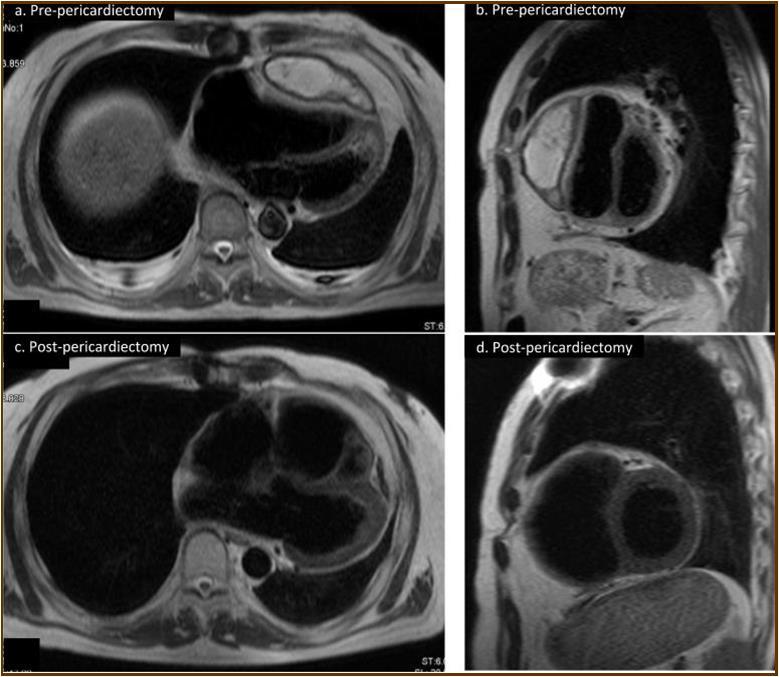

Figure 2.Magnetic resonance imaging findings. A thick cystic-like capsule which was tightly adhered to the right ventricle was seen (a. transverse view; b. sagittal view). A cystic-like capsule was removed after pericardiectomy (c. transverse view; d. sagittal view).

Magnetic resonance imaging findings. A thick cystic-like capsule which was tightly adhered to the right ventricle was seen (a. transverse view; b. sagittal view). A cystic-like capsule was removed after pericardiectomy (c. transverse view; d. sagittal view).

At the age of 52 years, the patient was admitted to our institution for both evaluation of heart failure and regular right heart catheterization including EMB. With respect to allograft rejection, ACR was again detected on regular EMB, and the immunosuppressive regimens were strengthened. Further echocardiographic investigations were conducted to explore the implications of findings indicative of constrictive physiology with thickened pericardium. Respiratory variation in both mitral and tricuspid inflow velocities was seen, but these findings did not meet the complete criteria for CP diagnosis (Figure 1c-e). Magnetic resonance imaging of the heart revealed seroma and a thick cystic-like capsule tightly adhered to the right ventricle (Figure 2a, b). Right heart catheterization revealed elevation of right atrial pressure with severely reduced cardiac index (Figure 3a). The classic dip-and-plateau pattern of right ventricular diastolic pressure and equalization of right atrial pressure and right ventricular diastolic pressure were also observed (Figure 3b). Based on these results, effusive CP or cardiac tamponade-like hemodynamics were strongly suspected, although the etiology remained unknown. Therefore, at 3 years post-HTx, the patient initially underwent removal of the seroma through exploratory lateral thoracotomy to elucidate the etiology of the disease. Yellowish fluid was found and the fluid was completely aspirated. Immunosuppressive regimens including everolimus, which may interfere wound healing, were temporarily converted to standard three-drug regimens. Removal of the seroma via lateral thoracotomy did not lead to improvement in symptoms or hemodynamics. Pathological analysis revealed fibrin and seroma, but no malignant cells or infection. Since the initial procedure did not have any effect on the patient’s symptom, pericardiectomy through median sternotomy was performed at two months after the initial procedure. Intraoperative findings indicated a thickened pericardium and effusion in front of the right ventricle. At first, after sternotomy and adhesiotomy, the tissue in front of the right ventricle, which appeared to be thickened parietal pericardium, was completely resected and the effusion fluid was removed. However, high central venous pressure (20 mmHg) persisted, resulting in a displacement of the left ventricle by the right ventricle. Therefore, additional tissue from the front of the right ventricle was excised, corresponding to diffusely thickened visceral pericardium and epicardium. After the procedure, central venous pressure decreased from 20 to 10 mmHg, and displacement of left ventricle resolved. Pathological analysis of the resected tissues demonstrated chronic fibrosis and chronic inflammation with plasma cells, but no infectious etiology was identified (Figure 4 a, b). After the pericardiectomy, hemodynamics (Figure 3a, c) and symptoms improved, and the patient is currently experiencing a favorable clinical course without complications.